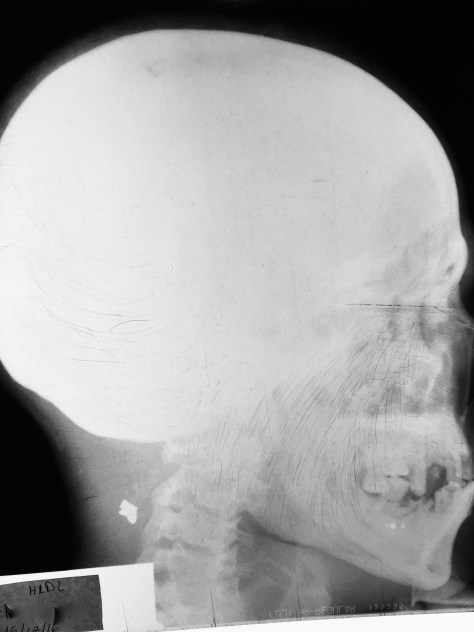

X-rays were done and we monitored his vital signs, which remarkably stayed stable despite our belief that a bullet had ‘un-brained’ him. The X-rays demonstrated the bullet lodged in the soft tissue of the back of his neck. Somehow, this bullet went through the bones of his face, missed his eye, his brain, his spine and spinal cord, all significant blood vessels and nerves, and probably some other anatomical parts I’ve forgotten since med school. This is what we refer to in medicine as ‘a miracle,’ a doctory-techno-jargon term.

the bullet:

That white spot behind his neck is the bullet.